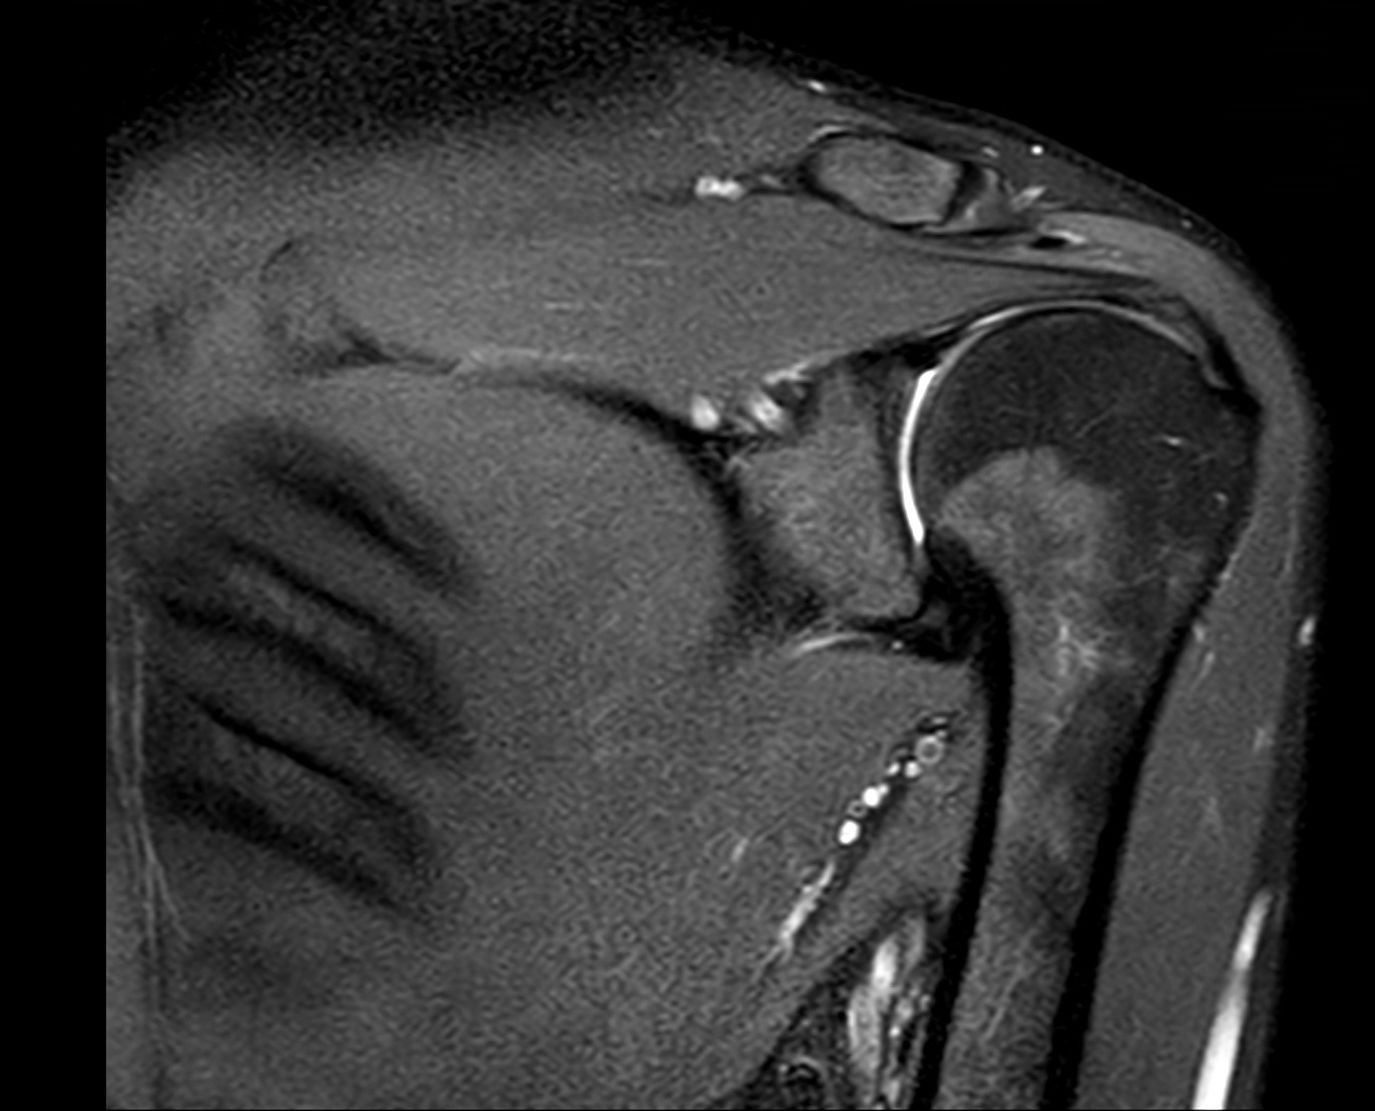

Az Észak-budai Szent János Centrumkórház Integrált Radiológiai Osztálya újabb fontos eszközzel gyarapodott, a vállízület vizsgálatára is alkalmas speciális tekercs biztosítja a korszerű betegellátást az MR-laborban.

A kórház szakemberei az első próbaméréseket sikeresen elvégezték, a berendezést megfelelően beállították, így a jövőben a már eddig is végzett ízületi vizsgálatok mellett a vállízület MR-vizsgálata is elérhető az intézményben.